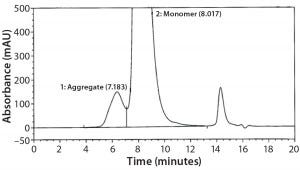

Figure 2: Size-exclusion chromatography with ultraviolet detection (SECUV)

data

SEC Analysis: All SEC data (pre- and postfill, and upon storage) show comparable percentages of high–molecular-weight (HMW) species for both the glass and Advasept vials (Figures 2–4).

Figure 3: Magnified size-exclusion chromatogram